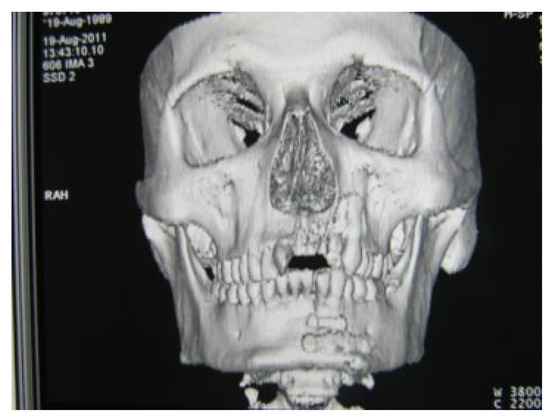

Superolateral Dislocation of Bilateral Intact Condyles—An Unusual Presentation: Report of a Case and Review of Literature

:1. Case Report